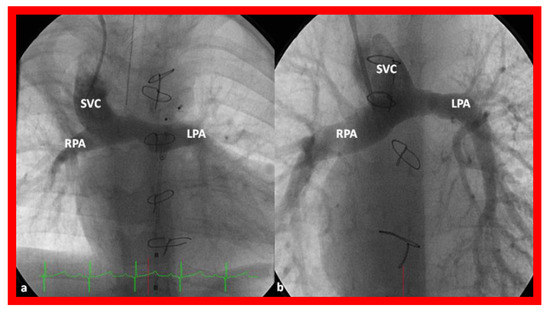

Independent of the nature of palliative intervention during the neonatal period, bidirectional Glenn operation [76] by anastomosis of the superior vena cava (SVC) to the right PA, end-to-side (Figure 14) is undertaken at an approximate age of six months. If a prior BT or Sano shunt is present, it is ligated at the time of bidirectional Glenn. While performing the procedure at six months is commonly accepted, the Glenn can be performed as early as three months subject to demonstrating normal PA pressures and anatomy.

Figure 14.

Cineangiographic frames illustrating bidirectional Glenn procedure, i.e., anastomosis of the superior vena cava (SVC) to the right pulmonary artery (RPA)] in two different children is shown in (a,b) (Stage II). Unobstructed blood flow from the SVC to the right (RPA) and left (LPA) pulmonary arteries is seen. Reproduced from Reference [33].

In babies who have persistent left SVC, bilateral bidirectional Glenn (Figure 15) is performed particularly in patients with a small or absent left innominate vein. A bidirectional Glenn procedure may also be undertaken for patients with infrahepatic interruption of the IVC with azygos or hemiazygos continuation, and such a procedure may be called the Kawashima procedure.

Figure 15.

Cineangiographic frames demonstrating a bilateral bidirectional Glenn procedure (Stage II). In (a), angiogram of the superior vena cava (SVC) illustrates opacification of the right pulmonary artery (RPA). The arrow in (a) shows the unopacified blood from a persistent left superior vena cava (PLSVC). In (b), an injection into the PLSVC illustrates opacification of the left pulmonary artery (LPA). The arrow in (b) shows the unopacified blood from the right SVC. Unobstructed flow from the respective SVCs into the pulmonary arteries is clearly seen. Reproduced from Reference [33].